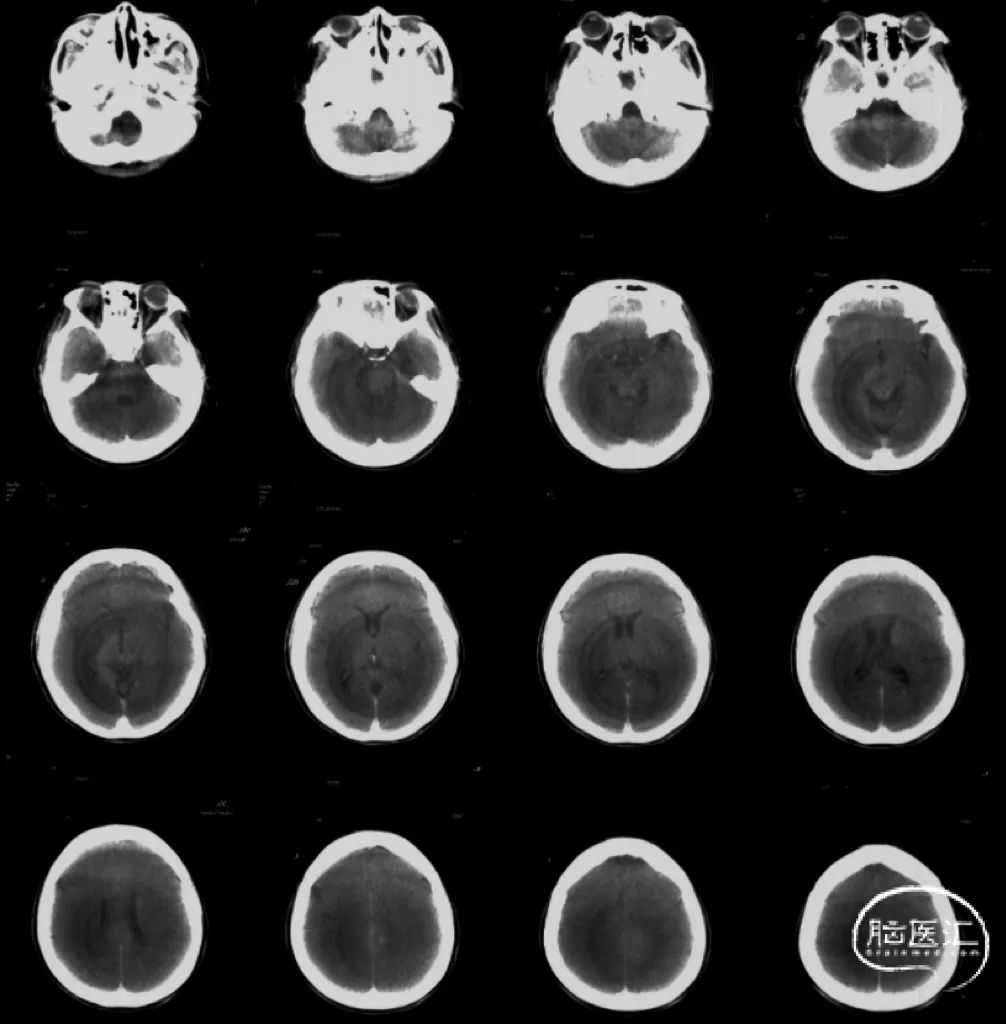

术后CT未见明显异常

术后CT未见异常,患者无新发神经功能障碍。